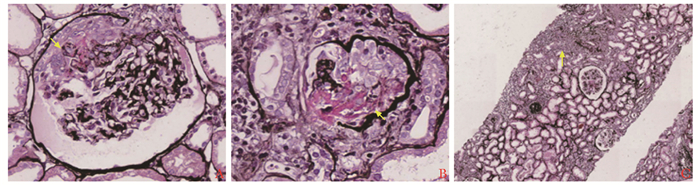

• 摘要: 本文报道一例肺、肾受累的抗中性粒细胞胞浆抗体(antineutrophil cytoplasmic antibodies, ANCA)相关性血管炎患者, 给予经典的糖皮质激素、环磷酰胺、血浆置换诱导缓解治疗有效。该患者在使用硫唑嘌呤维持治疗期间共出现2次感染, 后换用超小剂量(100 mg/次)利妥昔单抗维持治疗病情稳定。个体化利妥昔单抗治疗ANCA相关性血管炎效果显著, 同时避免了过度免疫抑制, 减轻了患者的经济负担。本例患者的诊疗经验有助于提高临床医生在ANCA相关性血管炎维持治疗方面的认识。

Abstract: We reported a case of ANCA-associated vasculitis with pulmonary and renal involvement that was effectively treated with glucocorticoids, cyclophosphamide, and plasma exchange therapy. The patient suffered two infections during maintenance treatment with azathioprine and was later switched to ultralow-dose (100 mg) rituximab to keep the disease in remission. Individualized rituximab therapy is effective in treating ANCA-associated vasculitis, while avoiding excessive immunosuppression, and reducing the financial burden. The diagnosis and treatment of this patient may help clinicians improve their understanding of maintenance therapy for ANCA-associated vasculitis.